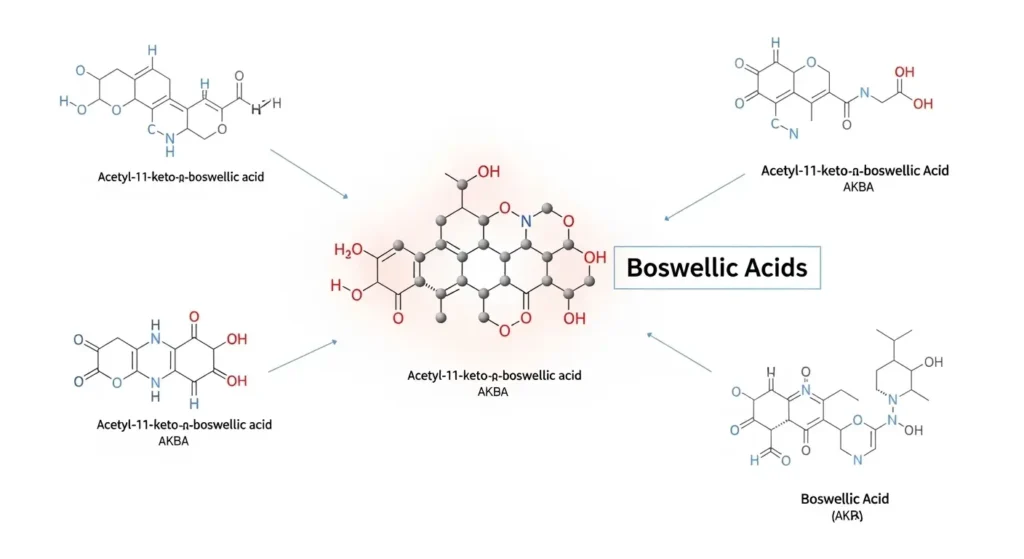

Active Compounds: Boswellic Acids

Boswellia benefits come primarily from boswellic acids, a group of pentacyclic triterpene compounds.

Key Boswellic Acids:

AKBA (Acetyl-11-keto-β-boswellic acid):

- Most potent anti-inflammatory compound

- 5-LOX enzyme inhibitor (unique mechanism)

- Found in 1-3% of raw resin

- Standardized extracts concentrate to 10-30% AKBA

KBA (11-keto-β-boswellic acid):

- Second most important compound

- Also inhibits 5-LOX

- Anti-inflammatory and analgesic

Other Boswellic Acids:

- β-boswellic acid

- Acetyl-β-boswellic acid

- Multiple supporting compounds

Why AKBA Matters: Research from Phytomedicine shows AKBA is the primary active compound responsible for boswellia’s anti-inflammatory effects. Quality supplements should be standardized to AKBA content.

What is AKBA in boswellia?

AKBA (Acetyl-11-keto-β-boswellic acid) is the most potent anti-inflammatory compound in boswellia, responsible for 5-LOX enzyme inhibition. Quality supplements should contain at least 10% AKBA, with 20-30% being excellent. AKBA-enriched extracts (5-LOXIN®, ApresFlex®) provide higher concentrations and better clinical results.